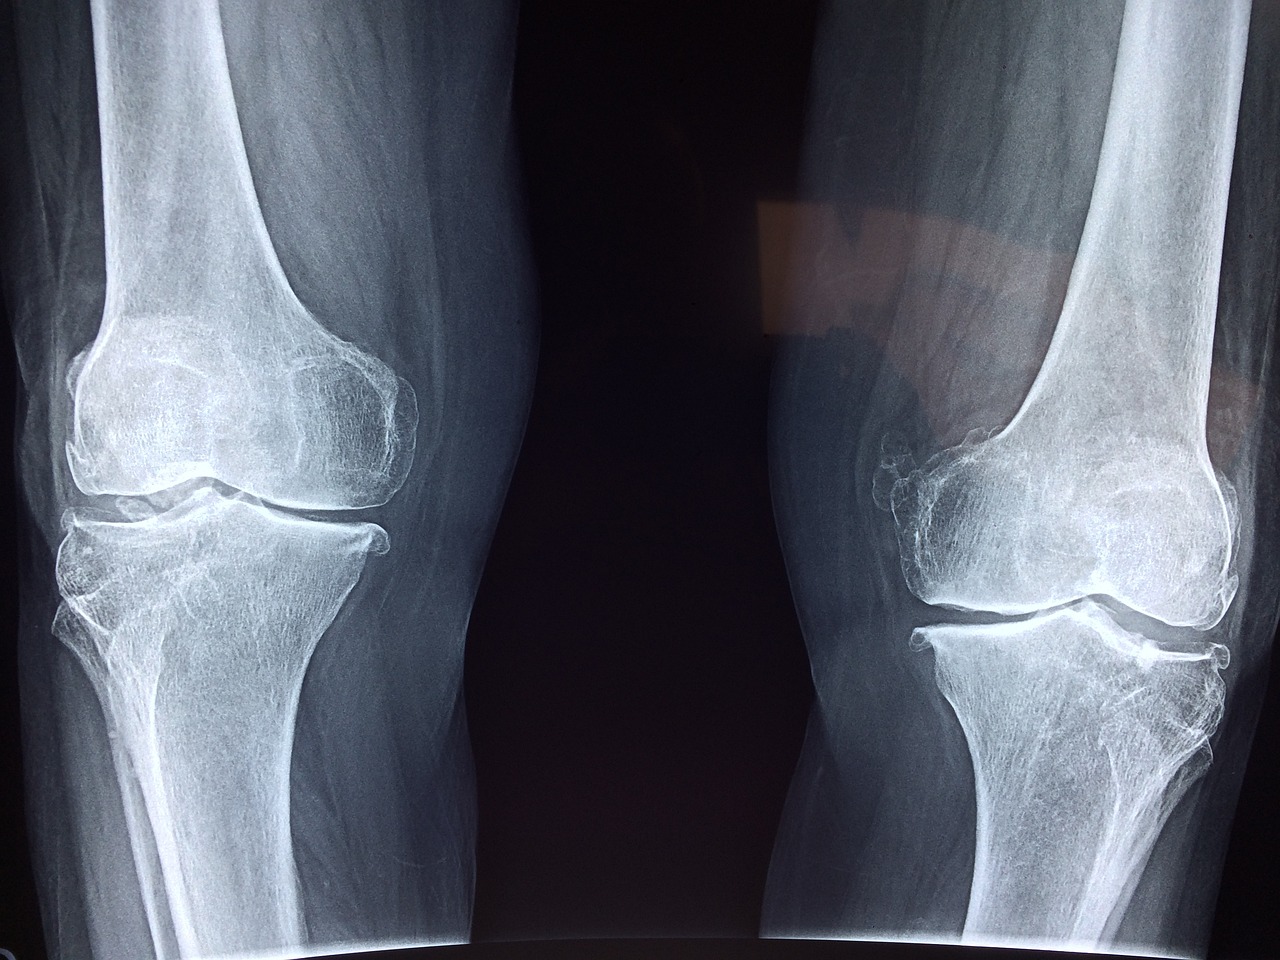

통풍은 고뇨산염의 농도가 높아지거나 요산의 배출이 제대로 이루어지지 않아 관절에 요산 결정이 쌓이는 질환입니다. 통풍을 관리하기 위해 다음과 같은 음식을 고려할 수 있습니다.

통풍은 관절에 요산 결정이 쌓여 발생하는 질환으로, 관절의 염증과 통증을 유발할 수 있습니다. 통풍을 관리하기 위해 다음과 같은 운동을 고려할 수 있습니다: